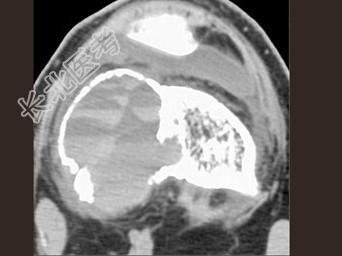

- 单项选择题男,24岁, 左大腿及膝部痛,结合图像, 最可能的诊断是 ( )

A、骨巨细胞瘤

B、骨囊肿

C、成软骨细胞瘤

D、动脉瘤样骨囊肿

E、骨肉瘤